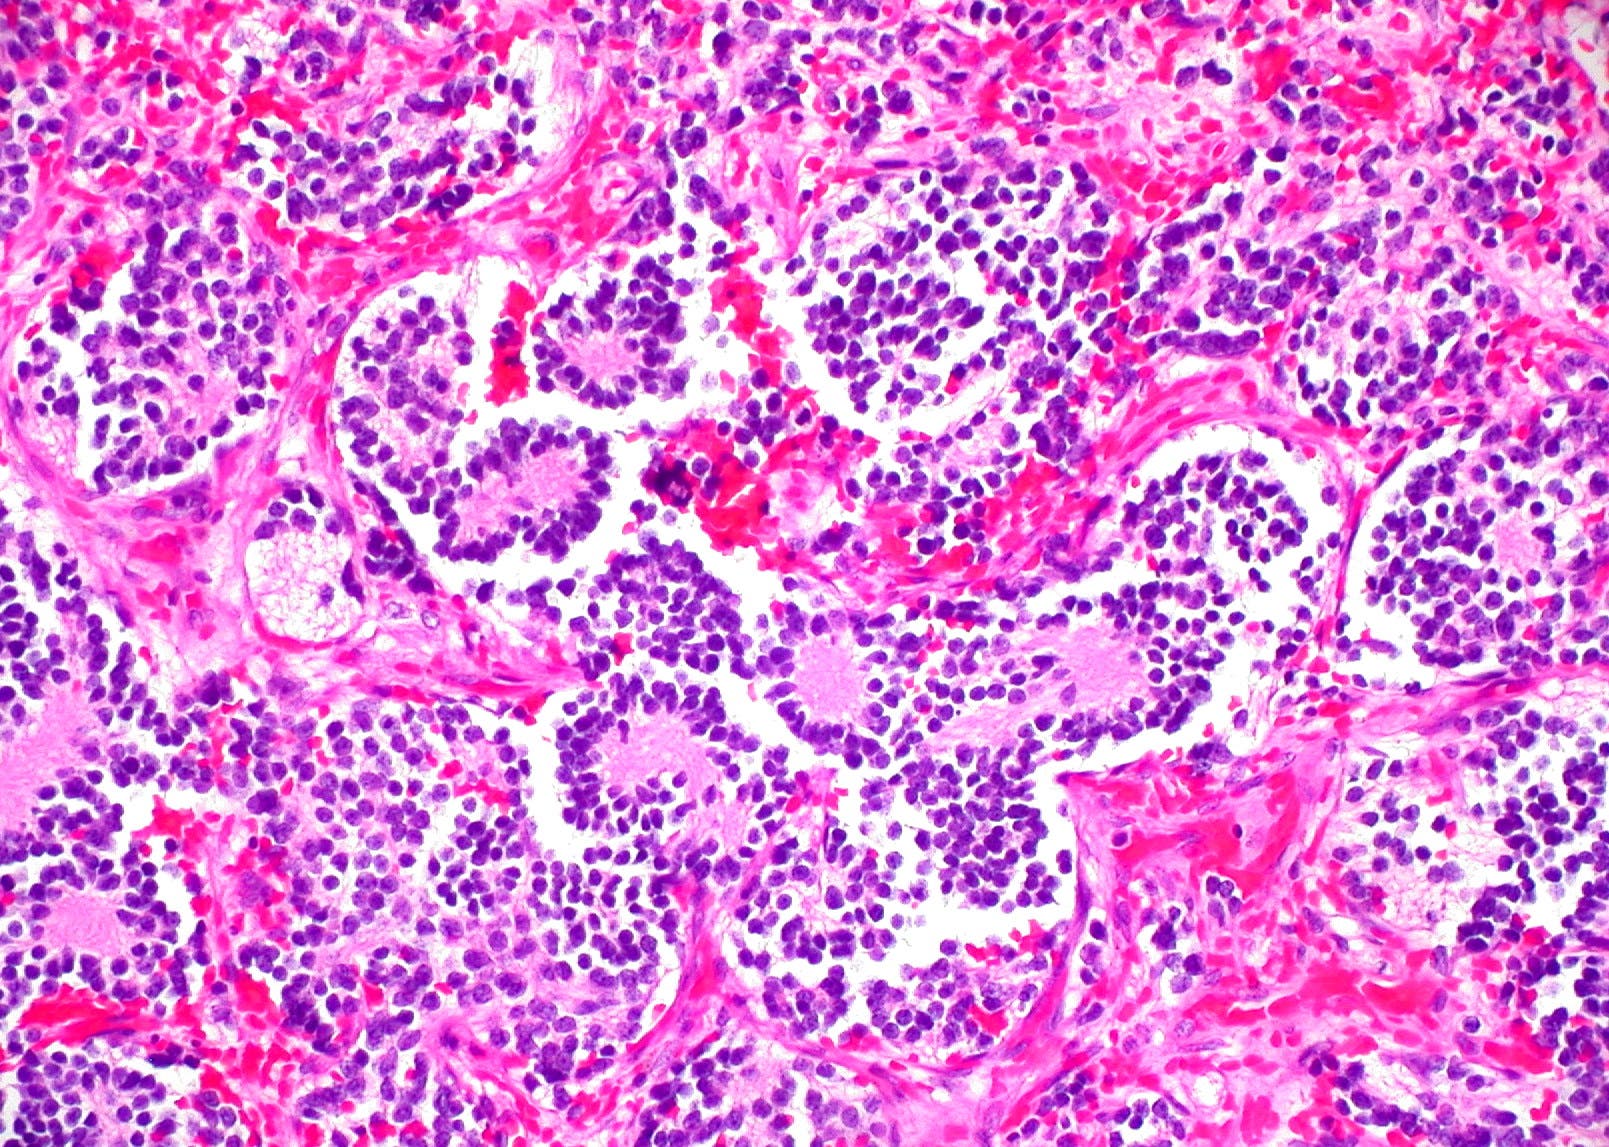

Hasta el momento, se han generado estructuras con gelatina y distintas cantidades de alginato metacrilado para recrear entornos tumorales de distinta rigidez. En estas estructuras se han cultivado células de neuroblastoma junto a otras no cancerosas que forman parte del conjunto tumoral, recreando así las interacciones que hay entre las distintas células del tumor y el ambiente que las rodea.

Estos modelos se procesaron como los tumores de los pacientes y se estudió su comportamiento mediante análisis de imagen digital microscópica. Los resultados indican que la proliferación celular, la producción de vitronectina y la expresión de genes relacionados con la migración depende de las condiciones del modelo y son específicas del tipo celular. Además, se ha visto cómo la presencia de células no cancerosas en los modelos modifica el comportamiento de las células tumorales.